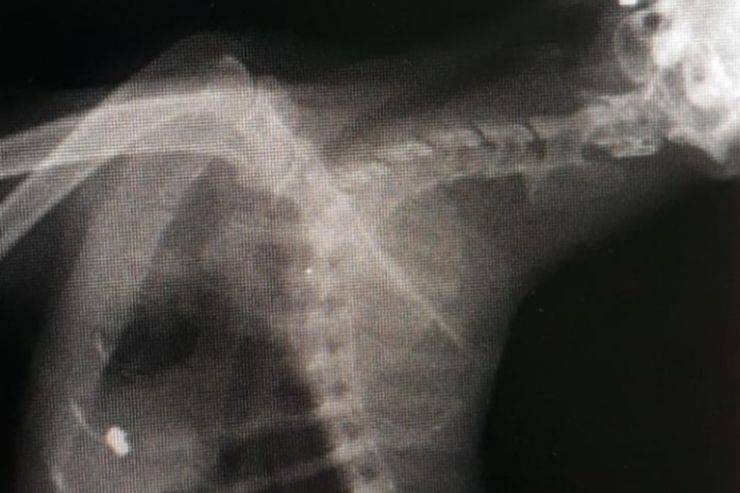

Quei brutti pallini di piombo nel corpicino: il gatto viene sottoposto all’operazione

Ed è qui che inizia la brutta storia. Portoghese viene sottoposto a una ecografia approfondita. Appena escono i risultati la coppia e la veterinaria in questione rimangono non solo a bocca aperta, ma con l’amaro intorno. Il gatto aveva tre pallini di piombo sparsi per il corpo. Un vero e proprio trauma, un po’ per tutti. La decisione della coraggiosa veterinaria però è stata decisiva: operazione d’urgenza. Il micio è andato “sotto i ferri” con grande grazie e l’intervento, molto delicato, è riuscito alla perfezione. La coppia era sconvolta, l’unica ad aver rilasciato una breve intervista è stata la stessa veterinaria, la dottoressa Giulia Roncetti: “Non avevo mai visto una cosa simile prima di oggi. Di solito queste cose, in un quartiere residenziale come Portoghese, non accadono mai. Secondo me il gatto è stato colpito da qualcuno qui intorno che lo ha sicuramente intrappolato in un primo momento. Difficile pensare che un micio grande come questo possa essere stato ‘fregato’ tre volte”.